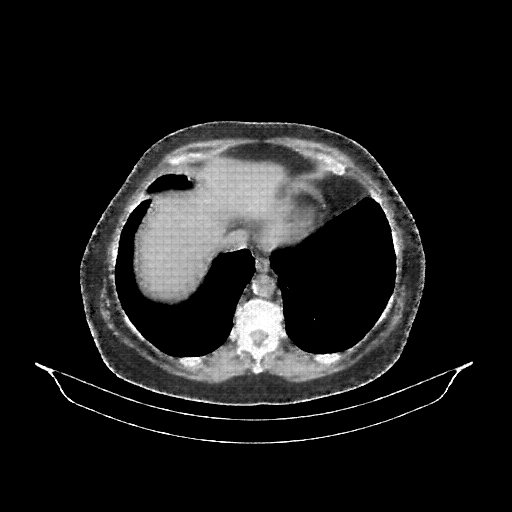

Image Grid

4Γ—3 grid: Rows show different image types (Original NATIVE, Reconstructed NATIVE, Original VENOUS, Generated VENOUS), Columns show windowing techniques (No Window, Lung Window, Mediastinum Window)

Original NATIVE CT scan (input)

Full window (WL 1023.5, WW 4095 β†’ Low βˆ’1024, High +3071)

Reconstructed NATIVE CT scan (cycle consistency)

Original VENOUS CT scan

Generated VENOUS CT scan (A→B translation)